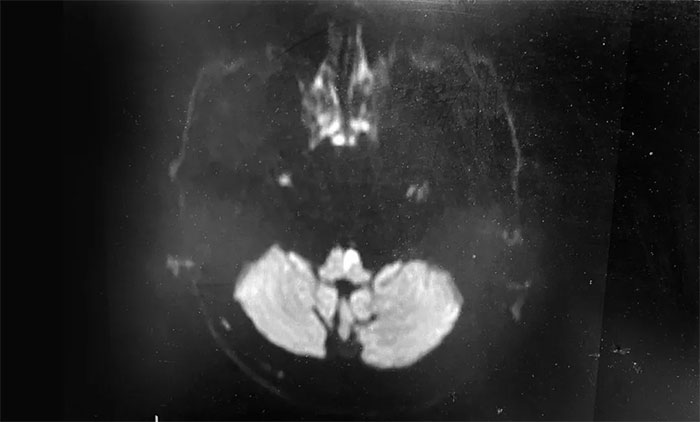

不出所料,MR基底動脈HRMR+DWI顯示,腦干(橋—延髓交界左側份)急性期腔隙梗死;左側椎動脈V4段次閉塞。這進一步印證了張靜波主任的判斷——椎基底動脈系統(tǒng)狹窄引起急性的腦干梗死。

▲ 腦干(橋—延髓交界左側份)急性期腔隙梗死